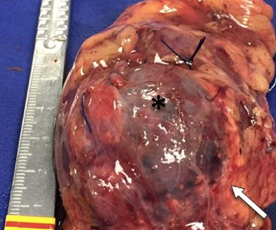

Imágenes y Cirugía

|

Pablo Sanchez Acedo, Cruz Zazpe Ripa, Antonio Tarifa Castilla, Ines Eguaras Córdoba, Javier Herrera Cabezón